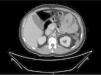

Varón de 49 años con extirpación de melanoma nodular estadio IIA en el brazo izquierdo hace 2 años. Acude por dolor abdominal epigástrico de 2 semanas de evolución, fiebre nocturna y síndrome constitucional. Analíticamente destaca anemia microcítica: hemoglobina 8.9g/dl, volumen corpuscular medio 73.7fl; elevación de proteína C reactiva: 220mg/l. La tomografía computarizada (TC) abdominal describe dilatación aneurismática intestinal junto a múltiples adenopatías regionales mesentéricas (figs. 1 y 2). Ante los hallazgos se realiza enteroscopia con doble balón donde se aprecia masa ulcerada, friable y dura a la toma de biopsias en primera porción yeyunal (fig. 3). En el diagnóstico diferencial también incluimos el linfoma primario intestinal, el tumor estromal gastrointestinal (GIST), el leiomiosarcoma y el adenocarcinoma. El estudio histopatológico concluye como metástasis intestinal de melanoma (figs. 4 y 5). Se realiza resección intestinal del segmento afecto y posterior inmunoterapia con nivolumab. La mayoría de los melanomas intestinales son metástasis de un melanoma cutáneo primario, con mejor pronóstico. En este caso, los antecedentes, los hallazgos endoscópicos y el análisis histopatológico aclararon el diagnóstico definitivo.